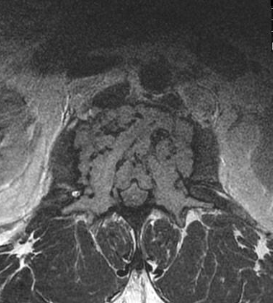

Osteosarcoma on X-ray (knee)